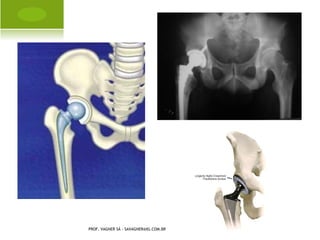

A RTROPLASTIA PARCIAL

PROF. VAGNER SÁ - SAVAGNER@IG.COM.BR

A RTROPLASTIA TOTAL